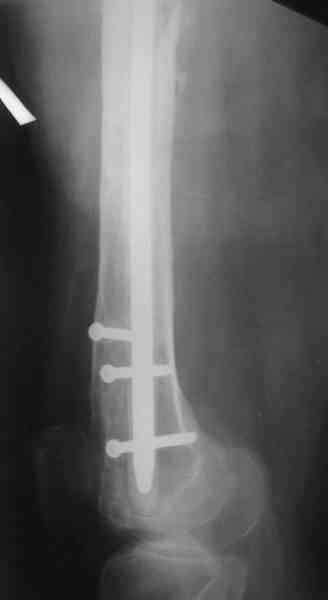

1, 2, 3, 4 - рентгенограммы бедра от 8 августа этого года (через четыре месяца после операции);

В качестве демонстрации лечения канального остеомиелита бедренной кости представляем пациентку (см. parts 2 и 3), которая как раз сегодня была у нас на контрольном осмотре. В мае этого года мы произвели ей фиксацию бедренной кости штифтом-спейсером по поводу ложного сустава и канального остеомиелита бедренной кости. Через 4 недели после операции свищи закрылись. Сейчас она ходит с полной нагрузкой на конечность.

4, 5, 6 - рентгенограммы бедра и фотографии пациентки (прошу прощения за низкое качество рентгеновских снимков) от 7 сентября 2007 г.